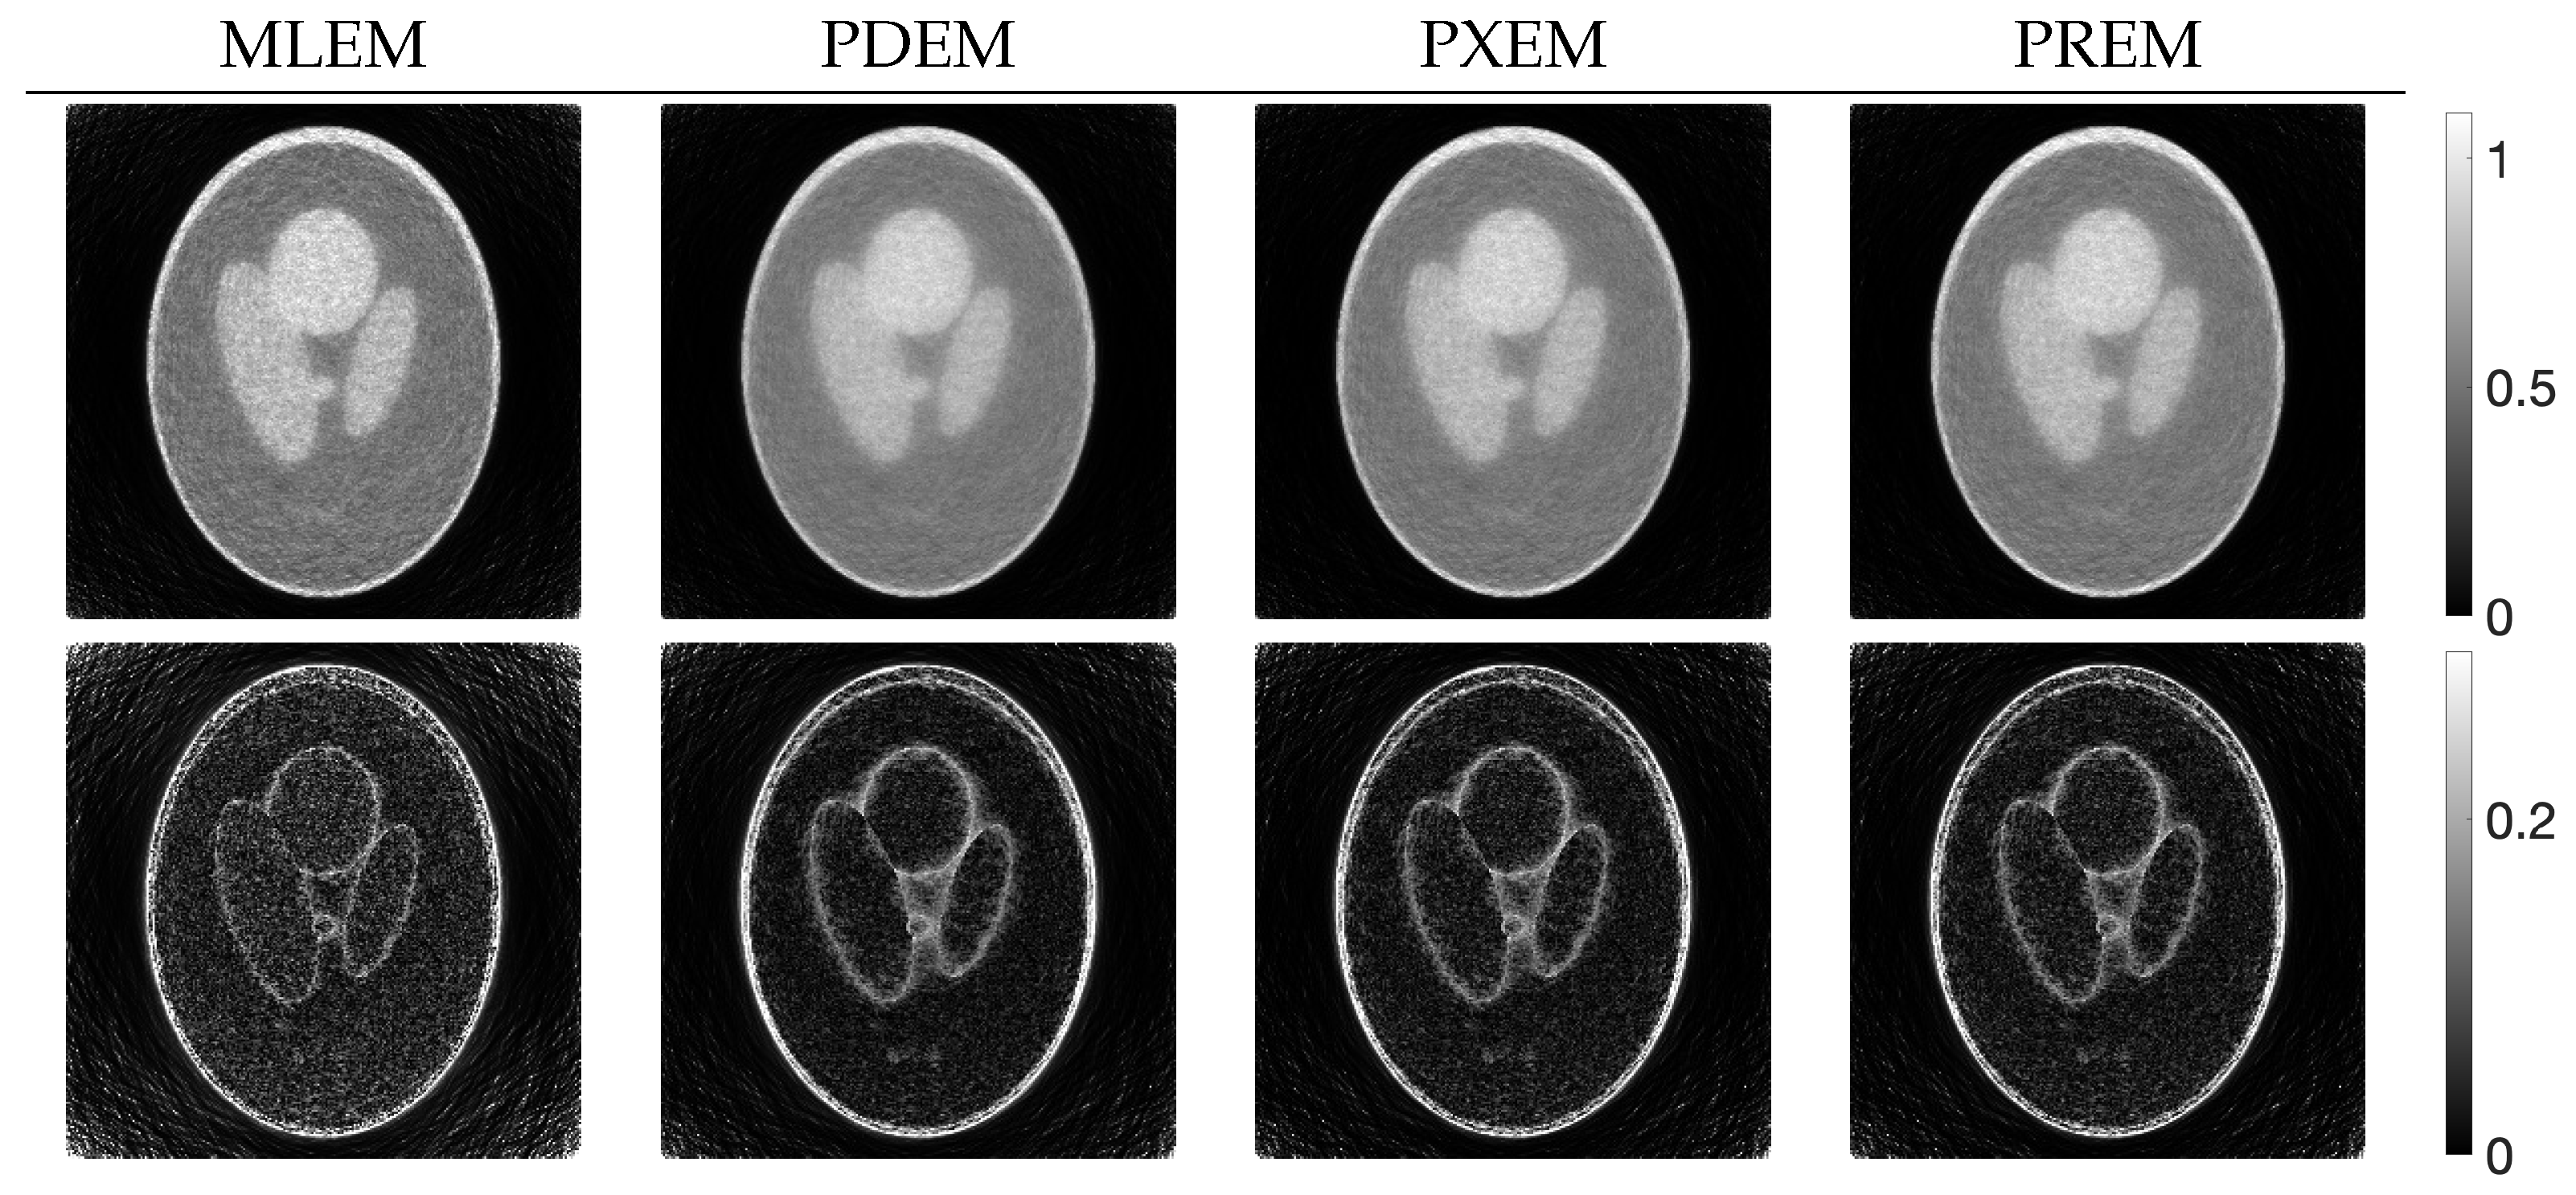

3.2. Experimental Results and Discussion

| MLEM | PDEM | PXEM | PREM | |

|---|---|---|---|---|

| std. dev. | 0.083 | 0.056 | 0.056 | 0.057 |

| contrast | 0.532 | 0.418 | 0.544 | 0.550 |